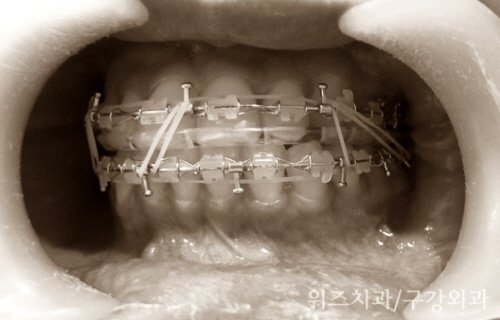

‘악간고정’이란 수술 전에 치아에 부착한 장치를 이용하여 위 아래 턱의 위치를 고정해주는 과정을 말한다. 흔히 입묶음 이라고 말하는 이 과정은 정상적인 교합의 조건을 갖춘 하악골 운동을 유도함으로써 빠른 시기에 턱의 기능이 회복되고 안정적인 위치에 고정되는 것을 도와 수술 후 다시 입이 벌어지는 현상이나, 회귀 성향 등 장기적인 합병증을 예방하는데 도움을 주는 필수적인 과정이다.

턱의 위치가 달라지는 턱교정 수술 이후에 악간고정이 필수적인 것은, 뼈를 둘러싸고 있는 연조직과 근육도 턱뼈의 변화에 적응하도록 도와야 하기 때문이다. 턱뼈, 연조직, 근육이 모두 새로운 위치에, 수술받은 사람에게 가장 편안하도록 자리 잡아야 하는데, 그러기 위해서는 수술 후 악간고정이 필수적인 것이다. 양악수술 전문병원에서 악간고정을 고집하는 것은 환자의 빠른 회복과 정상적인 기능회복을 앞당기기 위한 것이다.